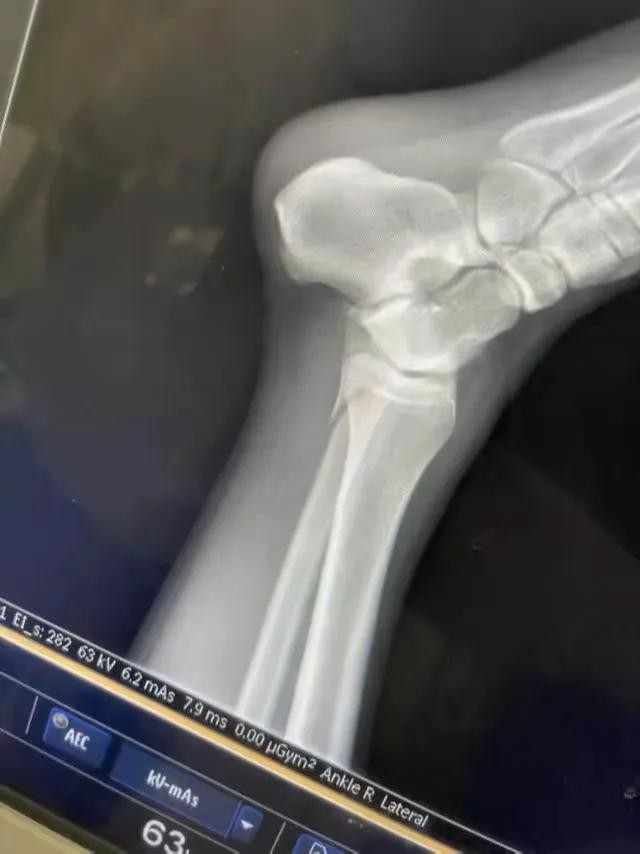

近期,有受伤的女孩在视频平台上直播,讲述了自己参加《快乐向前冲》时受伤的过程。她声泪俱下地回忆道:“我冲关时摔了下来,腿都骨折了。那一刻,我真的好害怕。”

这并非孤例。在《快乐向前冲》的赛道上,类似的受伤事件时有发生。有的选手在冲刺过程中扭伤脚踝,有的因为重心不稳而摔倒在地。